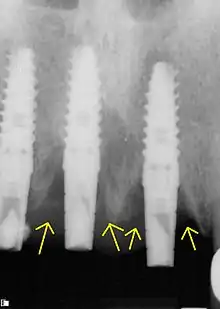

La péri-implantite est la perte progressive de l'os péri-implantaire à la suite d'une réaction inflammatoire[1].

Le risque de péri-implantite est accru lors de la mise en place d'un implant dentaire. La réaction inflammatoire pouvant survenir à la suite du déséquilibre de l'environnement intra-oral induit cette perte osseuse. Il s'agit de la principale source de complications à moyen et long terme des implants dentaires[2]. Selon l'étude Roos-Jansåcker ayant suivi un échantillon de patients, une péri-implantite apparaît dans 16 % des cas de mucosité chez ces derniers (48 % des patients) après 9 à 14 années d'implantation[2],[3].

Une étude de 2009 par Wilson TG Jr (2009) affirme que 25 % des prothèses scellées présentent des excès de ciment, 81 % des péri-implantites seraient dues à ces excès et qu'après le retrait des excès et nettoyage, 74 % de ces implants ne présentent plus de signe de péri-implantite[4].